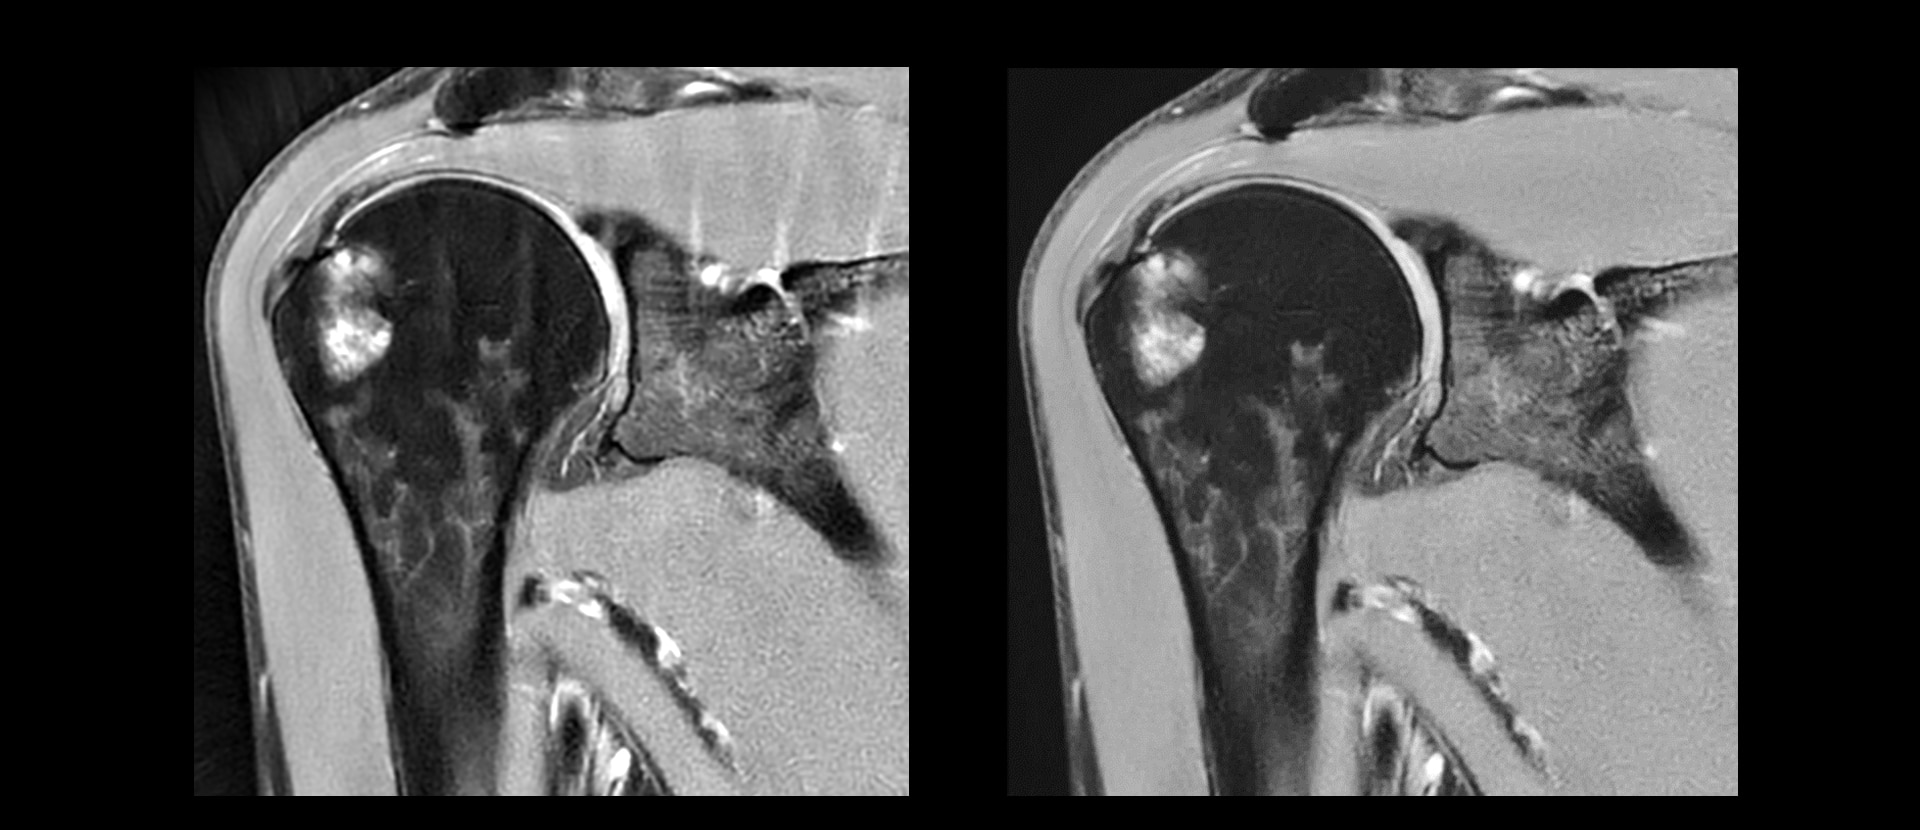

- Removes image noise and ringing by leveraging raw image data